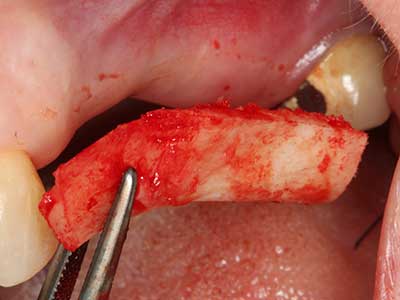

Indication: Bone harvesting

Autologous bone transplants are used in the form of blocks, shells, rings and are also combined with bone replacement materials as chips. If the implant site is prepared at the same time as the augmentation, various bone filter systems have proven effective for collecting the resulting bone chips. As an alternative, the implant site can be prepared using a low-speed device without irrigation. If an implant is not inserted, bone chips can be harvested from the periphery with bone scrapers. This is also possible with piezosurgery using specialized attachments that yield higher-quality bone chips than chips harvested with round drills, as has been confirmed in a study comparing the two methods (Chiriac, Herten et al. 2005).

Piezosurgery has additional advantages when harvesting bone blocks. In addition to the high precision with osteotomy described above, the use of the thin saw tips specifically minimizes loss of material. Greater loss of material during harvesting can be expected with the thicker instrument tips, particularly when using Lindemann drills (Lakshmiganthan, Gokulanathan et al. 2012). The basal separation, which is necessary particularly for retromolar block transplants, is simplified by specially designed rectangular saws, with the result that piezosurgery is viewed as a precise, simple and safe procedure for harvesting retromolar bone blocks (Happe 2007) (Fig. 1-12).

Fig. 3: Basal separation of the block is easier with specially angled attachments.